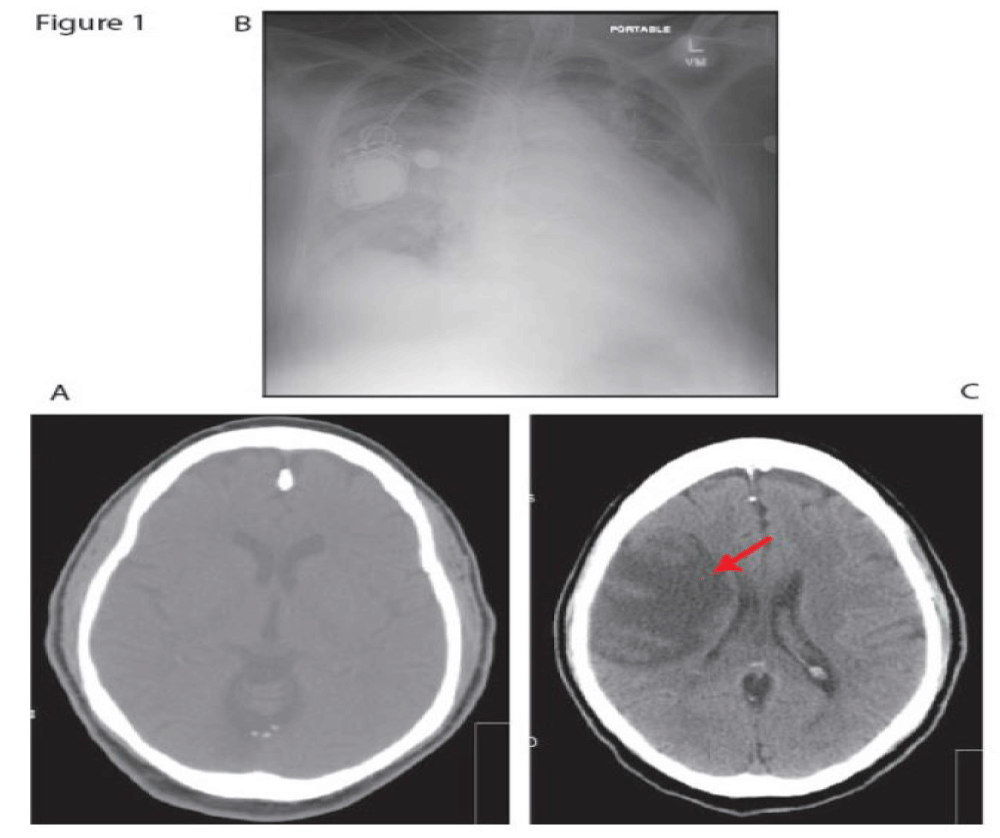

Neurogenic Pulmonary Edema: (TIA complicated with Acute Pulmonary Edema)

Getaw Worku Hassen1*, MD, PhD, Dennis Brown2, MD,Golnar Pashmforoosh1, MD, Frosso Adamakos1, MD, Tracy Barry1, DO, Rajnish Jaiswal1, MD, Leidy Gonzalez1, MD, Roger Chirurgi1 and Hossein Kalantari1

Neurogenic pulmonary edema (NPE) is a rare clinical entity that is seen in the setting of epileptic seizure, head injury and cerebral hemorrhage. NPE in the setting of transient ischemic attack (TIA) has not been reported before.